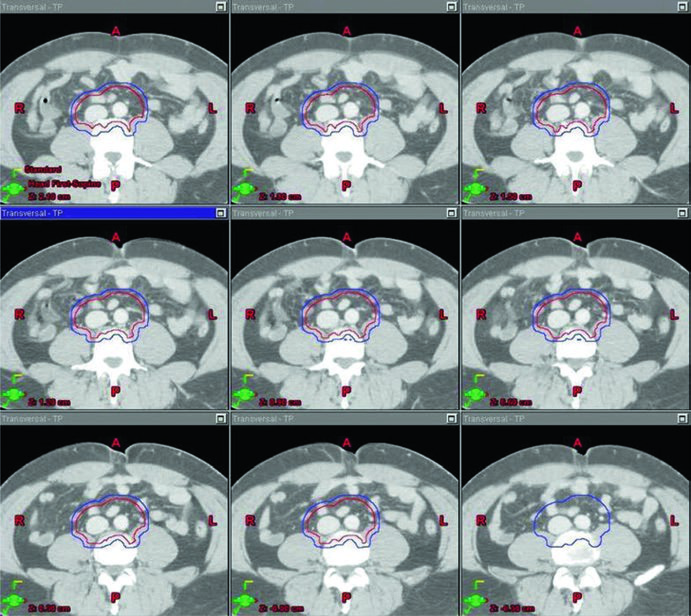

O ponto técnico mais útil é que o dogleg não nasce do zero. Ele começa com o mesmo contorno de cava inferior e aorta usado no estágio I e, em seguida, incorpora vasos ilíacos comuns, porções proximais dos ilíacos internos até a emergência da glútea superior e vasos ilíacos externos até a borda superior do acetábulo, com expansão de 1,2 cm respeitando limites anatômicos. Depois disso, o capítulo pede contorno da doença nodal grosseira, o GTV, com expansão de 0,8 cm respeitando a anatomia, formando um CTV nodal. A união do CTV vascular com o CTV nodal produz o CTV inicial.

Esse campo inicial recebe expansão de 0,5 cm mais 0,7 cm até a borda do bloco para compor o PTV inicial, ainda na faixa de 20 a 25,5 Gy com frações de 1,5 a 2,0 Gy. O boost em conedown segue a mesma lógica geométrica aplicada ao CTV nodal, também com 0,5 cm mais 0,7 cm até a borda do bloco, até completar 30 a 36 Gy em 2 Gy por fração. O capítulo ainda acrescenta uma regra simples e prática para a doença visível: garantir margem de 2 cm ao redor de toda adenopatia grosseira visível.

Os marcos anatômicos ajudam a não perder o eixo do campo. Superiormente, o limite permanece no topo de T11, com a mesma nota de que algumas fontes usam topo de T12. Inferiormente, o capítulo posiciona o limite no topo do acetábulo, embora algumas fontes recomendem o meio ou a base do forame obturatório. A borda lateral acompanha as pontas dos processos transversos das vértebras lombares, tipicamente em torno de L3, considerando a posição dos rins, e se estende inferiormente para cobrir a borda lateral do acetábulo. Para seminoma à esquerda, a cobertura do hilo renal esquerdo volta a aparecer como opcional.

A figura de boost fecha esse raciocínio muito bem. Ela mostra, em um exemplo de estágio IIA, a diferença entre GTV em amarelo, CTV em vermelho e PTV em azul. Não é só uma ilustração bonita; é a prova visual de que o capítulo separa volume eletivo, volume inicial e volume de reforço com precisão suficiente para orientar planejamento real.

| CTV inicial | Usar os mesmos contornos e expansões de cava inferior e aorta descritos na Table 27.1. Depois, contornar vasos ilíacos comuns, porções proximais dos ilíacos internos até a origem da glútea superior e vasos ilíacos externos até a borda superior do acetábulo, com expansão de 1,2 cm respeitando limites anatômicos. Contornar a doença nodal grosseira (GTV) e expandir 0,8 cm respeitando limites anatômicos. Combinar CTV vascular e CTV nodal para formar o CTV inicial. |

Borda superior: topo de T11 (algumas fontes recomendam topo de T12) [6]. Borda inferior: topo do acetábulo (algumas fontes recomendam meio ou base do forame obturatório) [6]. Borda lateral: pontas dos processos transversos lombares, tipicamente em L3 com consideração da localização renal, estendendo-se para cobrir a borda lateral do acetábulo na porção inferior do campo. |

| PTV inicial 20–25,5 Gy em 1,5–2,0 Gy por fração |

Expandir o CTV inicial em 0,5 cm + 0,7 cm até a borda do bloco. | Para seminoma à esquerda, os estudos de mapeamento nodal sugerem que cobrir o hilo renal esquerdo é opcional [7]. |

| PTV de boost em conedown Total de 30–36 Gy em 2 Gy por fração |

Expandir o CTV nodal em 0,5 cm + 0,7 cm até a borda do bloco. | Garantir margem de 2 cm ao redor de toda adenopatia grosseira visível. |